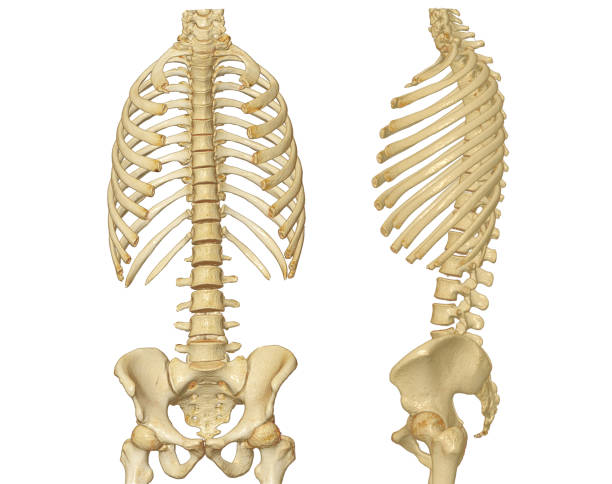

척추관협착증은 척추의 퇴행성 변화로 인해 발생합니다.

이 질환은 척추 내의 신경관이 좁아지면서 다양한 증상을 일으킵니다.